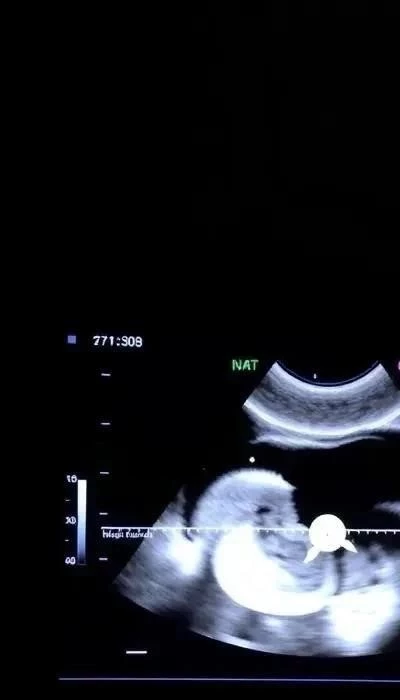

УЗИ второго триместра – это детальное ультразвуковое исследование, которое позволяет оценить анатомию плода и выявить возможные структурные аномалии. Врач УЗИ оценивает такие параметры, как копчико-теменной размер (КТР), толщина воротникового пространства (ТВП), состояние носовой кости, размеры сердца и почек, а также другие органы и системы плода. Увеличенная толщина воротникового пространства может быть признаком хромосомных аномалий, но также может быть связана с другими факторами.

УЗИ второго триместра – это важный этап скрининга, позволяющий оценить анатомию плода и выявить возможные пороки развития. Проводится исследование обычно между 18 и 22 неделями беременности. Врач УЗИ оценивает целый ряд параметров, каждый из которых имеет свои нормы, зависящие от срока беременности.

КТР (копчико-теменной размер) – это расстояние от копчика до темени плода. По КТР определяется гестационный возраст и оценивается соответствие развития плода сроку беременности. Отклонения от нормы могут указывать на задержку или опережение развития.

ТВП (толщина воротникового пространства) – это измерение пространства в области шеи плода. Увеличенная ТВП может быть признаком синдрома Дауна или других хромосомных аномалий. Нормальные значения ТВП варьируются в зависимости от срока беременности, но обычно не превышают 2.5 мм.

Носовая кость – ее наличие и правильная форма также важны. Отсутствие или гипоплазия (недоразвитие) носовой кости может быть связано с синдромом Дауна. Сердце плода тщательно исследуется на предмет наличия врожденных пороков. Почки оцениваются по размеру, форме и структуре.

Другие важные параметры: врач УЗИ оценивает размеры головного мозга, наличие конечностей, состояние желудочно-кишечного тракта и мочевой системы плода. Также оценивается количество околоплодных вод и состояние плаценты. Важно! Обнаружение каких-либо отклонений не всегда означает наличие серьезных проблем. В некоторых случаях требуется повторное УЗИ или консультация узких специалистов.